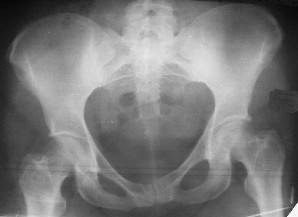

Из анамнеза: в ноябре 2002г. оступилась,упалана трап самолета (на верхней площадке, сразу при выходе из салона) на правый тазобедренный сустав, а затем - вниз на землю на ноги и ягодицы. Потеряла сознание от боли. Доставлена в больницу по месту жительства, лечилась консервативно с диагнозом кокцигодиния.На рентгенограмме от 27.11.02г. вывиха копчика не определяется (снимок идентичен представленной R-грамме от28.11.03г., кроме этого есть нормальная R-грамма копчика в боковой проекции).Через три недели стала ходить, но привести правую ногу в тазобедренном суставе не могла. Сейчас ходит отведя кнаружи правое бедро и голень, как ножку циркуля (фото 1). Неврологических нарушений нет. По просьбе врачаможет на 30-40 секунд поставить ноги вместе (фото 2). При этом испытывает сильную тянущую боль и ощущение "вывернутости" в правом тазобедренном суставе. Эти ощущения заставляют вновь отвести бедро. В положении лежа разогнуть бедро полностью не может из-за болей в ягодичной мышце (фото 3). Сгибание также ограничено из-за болей (фото 4). Отведение в положении лежа возможно в том же объеме, что и стоя (фото 5). Заподозрен старый разрыв правого крестцово-подвздошного сочленения.Выполнено R-исследование и КТ(в приложении). По-поводу деформации лонного сочленения выяснен гинекологический анамнез. Роды одни, нормальные в 22 года. Из роддома выписана на 8 сутки, нарушения походки не было, R-графия таза не проводилась. Вопросы на обсуждение: 1. Диагноз либо алгоритм дальнейшего обследования. 2. Лечебная тактика (в первую очередь возможность и целесообразность оперативного лечения).

Уважаемый Юрий Алексеевич, сделаны ли пациентке более дистальные срезы КТ с захватом области тазобедренного сустава? Учитывая давность травмы, могли присоединиться и дистрофические процессы в субхондральной кости головки и впадины. Изменения в капсуле будут хорошо видны на УЗИ, особенно в сравнении со здоровой стороной. Эффективность лечебно-диагностического введения гормональных препаратов, на мой взгляд, сомнительна ввиду давности патологического состояния. При такой стойкой и давней контрактуре без операции вряд ли можно обойтись. Под наркозом амплитуда на разгибание должна увеличиться, усилить эффект можно тено-миотомиями заинтересованных групп мышц, капсулотомией + в послеоперационном периоде хорошее консервативное противовоспатлительное лечение с укладками на разгибание.Что мешает приведению пока не ясно, во встретившихся в нашей работе аналогичных ситуациях причиной был формирующийся медиальный остеофит головки, выталкивающий её из впадины.

Не исключена вероятность посттравматического изменения мышечной ткани (рубцы, спайки, оссификация и т.д.), которые приводят к уменьшению

эластичности этих мышц. В положении приведения происходит их перерастяжение, создается болевой синдром. На представленных снимках, к сожалению, эти структуры не определяются.